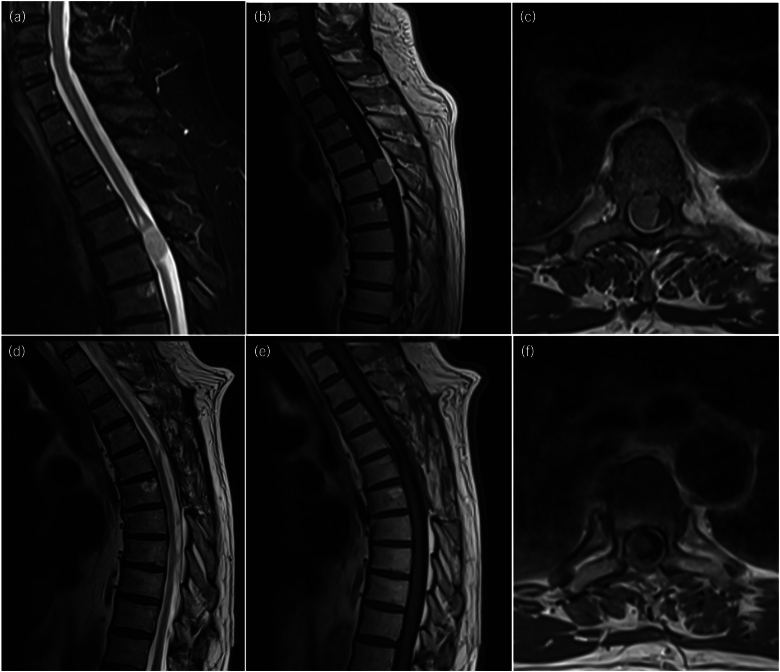

Our aim was to investigate the effectiveness of navigated transcranial magnetic stimulation (nTMS) brain mapping to characterise preoperative motor impairment caused by an intradural extramedullary (IDEM) tumour and postoperative cortical functional reorganisation. Preoperative and 1-year follow-up clinical, radiological and nTMS data from a case of thoracic spinal meningioma that underwent surgical resection of the lesion were collected and compared. A 67-year-old patient presented with severe progressive thoracic myelopathy (hypertonic paraparesis, clonus, insensate urinary retention) secondary to an IDEM tumour. Initial nTMS assessment showed bilateral upper limb representation with no positive responses for both lower limbs. He underwent successful surgical resection for his IDEM (meningioma WHO grade 1). At 1-year follow-up, the patient's gait was improved and his bladder function normalised. nTMS documented positive responses for both upper and lower limbs and a decrease in the area (right side: 1.01 vs 0.39cm2; left side: 1.92 vs 0.81cm2) and volume (right side: 344.2 vs 42.4uVcm2; left side: 467.1 vs 119uVcm2) of cortical activation for both upper limbs, suggesting a functional reorganisation of the motor areas after tumour resection. nTMS motor mapping and derived metrics can characterise preoperative motor deficit and cortical plasticity during follow-up after IDEM resection.

Abstract Image